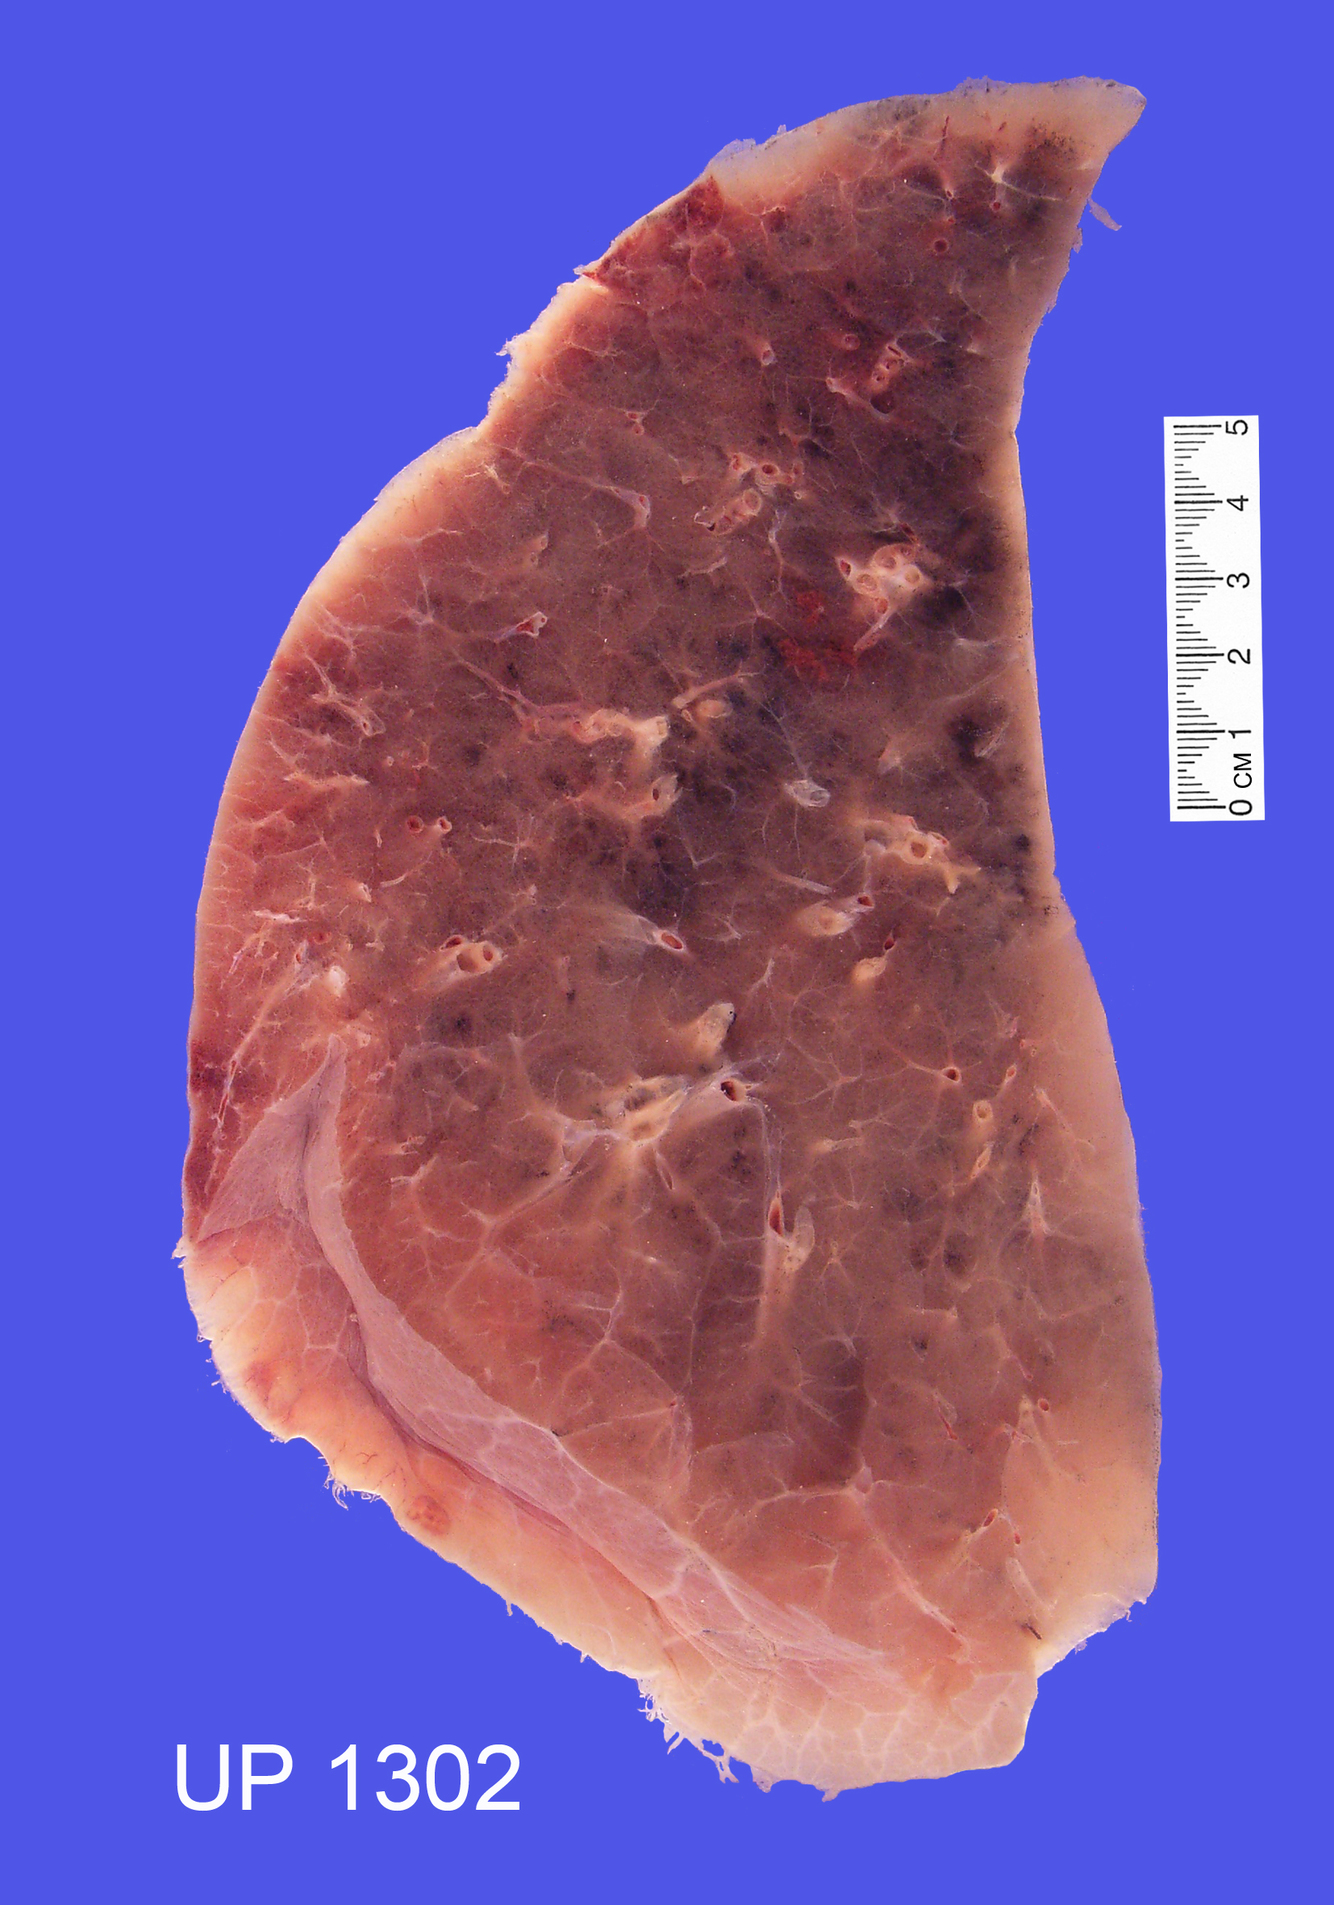

Describe the specimen

Normal Lung

The amount of anthracosis is normal for an adult

The pulmonary lobules are easily seen